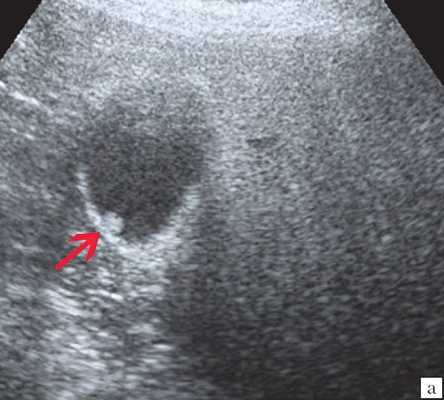

а) Полип размером 22 мм, с фестончатыми контурами, пониженной эхогенности, ложноположительная диагностика широкого основания из-за ограниченной смещаемости в просвете желчного пузыря.

a) Одиночный полип в желчном пузыре (гиперэхогенное пристеночное неподвижное образование, с ровными контурами, без акустической тени).

а) Одиночный конкремент желчного пузыря (подвижная гиперэхогенная структура, дающая четкую теневую дорожку).